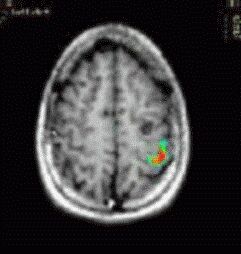

Caso 3

Paciente Paciente de sexo masculino de 14 años de edad, con convulsiones

Paradigma Tarea de dar golpecitos

ACTIVADO: Dar golpecitos con los dedos de forma alternada con la mano derecha

DESACTIVADO: No pensar en nada

Resultados La corteza del surco central izquierdo mostró una fuerte activación.  Las imágenes muestran claramente la relación con el tumor.

Comentarios El tumor se extirpó sin déficit motor postoperatorio.